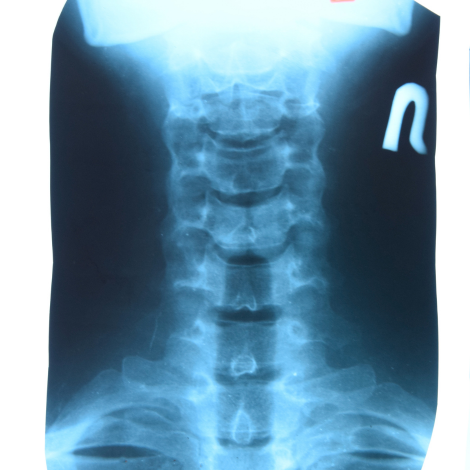

Cervical Spine X-ray

A cervical spine X-ray can help you find the cause of symptoms such as neck, shoulder, upper back, or arm pain, as well as tingling, numbness, or weakness in the arm or hand. It can detect fractures in the cervical vertebrae or dislocation of the joints between the vertebrae.